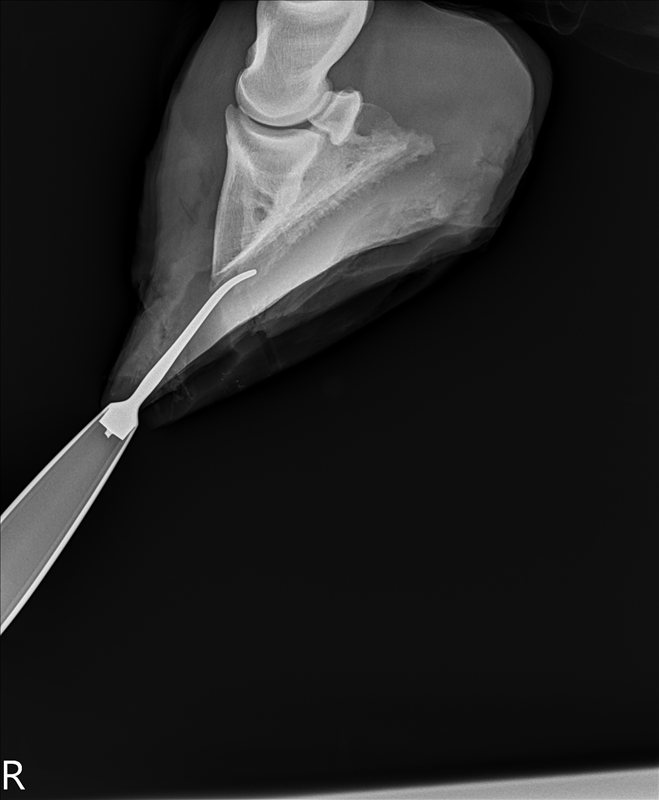

![]() |

| After surgery, with the hole and the missing coffin bone area. Not too bad, actually – there’s still bone in the middle, they didn’t take a clear slice out. |

| Side view of same. You can see the hole going up to the toe, and the scraping from both the top and bottom. |